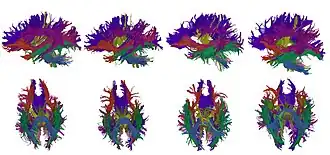

High-dimensional white matter atlas generation and group analysis: result of automatic segmentation of novel subjects.

High-dimensional white matter atlas generation and group analysis: result of automatic segmentation of novel subjects. -